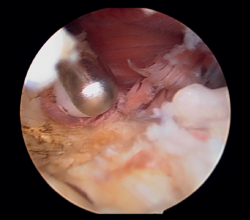

En primer lugar, se realiza el portal anteromedial de visión, incidiendo únicamente la piel y realizando disección roma con un mosquito recto. A continuación, se introduce la vaina del artroscopio, atravesando de forma anterior y proximal el septo fibromuscular medial, en dirección a la cabeza del radio, de forma posterior y distal, para evitar lesionar el nervio cubital y el paquete vascular anterior del codo. Una vez introducida la óptica en el portal medial, se procede a realizar el portal lateral proximal como portal de trabajo. Se realiza bajo visión directa, utilizando como guía una aguja intramuscular de fuera a dentro, para localizar el punto de entrada que permita mejor ángulo de trabajo (Figura 4). Posteriormente, se incide en la piel y se realiza disección roma con un mosquito recto para entrar en la articulación (Figura 5).

Figura 4. Posicionamiento con aguja del portal lateral (paciente en decúbito lateral, codo derecho, visión desde el portal medial).